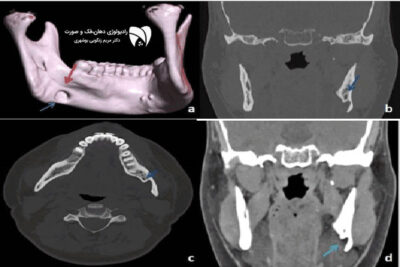

تحلیل حرکت فک یکی از جنبههای کلیدی در بررسی مشکلات فکی و دندانی است. با استفاده از تصویربرداری سهبعدی فک، دندانپزشکان و متخصصان ارتودنسی میتوانند حرکتهای دقیق فک را در شرایط مختلف مشاهده و بررسی کنند. این روش بهویژه در درمان ناهنجاری فک کاربرد دارد و دقت بالایی را در تشخیص مشکلات فکی فراهم میکند. تصویربرداری سهبعدی فک اطلاعات جامعی درباره موقعیت فک، میزان حرکت آن و نحوه تطابق آن با دندانها ارائه میدهد. تحلیل حرکت فک از طریق این روش باعث میشود که درمان ناهنجاری فک با دقت بیشتری انجام شود. استفاده از این فناوری در تحلیل حرکت فک به پزشکان کمک میکند که قبل از شروع درمان، یک برنامه درمانی دقیق را طراحی کنند. در نتیجه، تصویربرداری سهبعدی فک موجب کاهش خطاهای تشخیصی و بهبود کیفیت درمان ناهنجاری فک میشود.

تحلیل حرکت فک از طریق تصویربرداری سهبعدی فک یکی از روشهای نوین در پزشکی است که دقت تشخیص و درمان ناهنجاری فک را افزایش میدهد. این روش امکان مشاهده تغییرات جزئی در حرکت فک را فراهم کرده و اطلاعات دقیقی در مورد ساختار فکی ارائه میدهد. تصویربرداری سهبعدی فک به پزشکان اجازه میدهد که فرآیند درمان ناهنجاری فک را بهینهسازی کنند و نتایج بهتری را برای بیماران به ارمغان بیاورند. تحلیل حرکت فک از طریق این فناوری، امکان شناسایی مشکلات فکی در مراحل اولیه را فراهم میکند که این امر باعث جلوگیری از پیشرفت ناهنجاری فک میشود. همچنین تصویربرداری سهبعدی فک با کاهش نیاز به روشهای تهاجمی، باعث بهبود تجربه درمانی بیمار خواهد شد.

تحلیل حرکت فک با استفاده از تصویربرداری سهبعدی فک دارای مزایای متعددی است که بهبود دقت در درمان ناهنجاری فک یکی از مهمترین آنها محسوب میشود. تصویربرداری سهبعدی فک امکان مشاهده دقیق حرکات فکی را فراهم کرده و پزشکان را در طراحی روشهای درمانی بهتر یاری میکند. تحلیل حرکت فک با استفاده از این تکنولوژی، میزان جابجایی فک را در طول زمان مشخص میکند و به دندانپزشکان کمک میکند تا درمان ناهنجاری فک را با دقت بیشتری انجام دهند. تصویربرداری سهبعدی فک نهتنها به بهبود تشخیص کمک میکند، بلکه امکان اصلاح موقعیت فکی را با روشهای غیرتهاجمی نیز افزایش میدهد.

تحلیل حرکت فک یکی از جنبههای کلیدی در تشخیص مشکلات فکی است که با استفاده از تصویربرداری سهبعدی فک دقت بیشتری پیدا کرده است. تصویربرداری سهبعدی فک این امکان را فراهم میکند که درمان ناهنجاری فک به روش دقیقتر و مؤثرتری انجام شود. این روش، اطلاعات دقیقی درباره نحوه عملکرد فک در طول زمان ارائه داده و امکان بررسی تغییرات کوچک در تحلیل حرکت فک را فراهم میکند. تصویربرداری سهبعدی فک همچنین با کاهش نیاز به تصویربرداریهای متعدد، میزان تابش اشعه به بیمار را کاهش میدهد که این امر موجب افزایش ایمنی بیمار میشود. استفاده از این فناوری در درمان ناهنجاری فک به پزشکان کمک میکند که درمانی مؤثرتر و با نتایج بلندمدتتری را ارائه دهند.